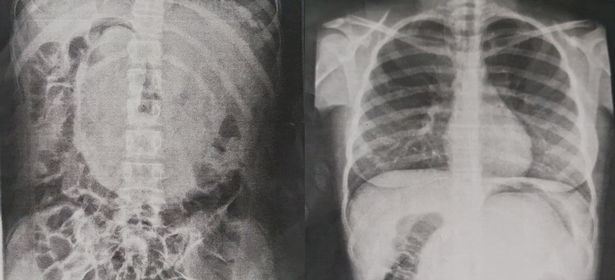

والدین ملیسا با وجود مراجعه به پزشکان متعدد، اثری از بهبودی را در دختر خود مشاهده نکردند. جکی افزود: "سرانجام با انجام آزمایش ایکس ری پزشکان متوجه توده بزرگ در شکم دخترم شدند. این در حالی بود که من نمیدانستم این توده چیست و یکی از همسایگانم به من گفت که من چند سال پیش در جایی خوانده ام که افرادی که اقدام به خوردن موهای خود میکنند، به این مشکل دچار میشوند."

ملیسا در تاریخ ۱ اکتبر تحت عمل جراحی قرار گرفت و پزشکان جراح با توجه به سنگین بودن این توده مو با برش آن به چهار قسمت این توده مو را یک به یک از شکم این نوجوان خارج کردند.